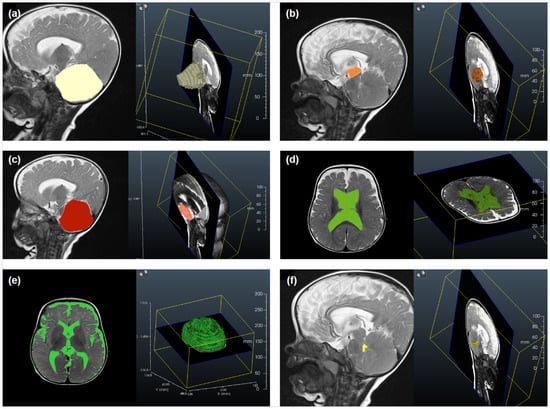

Illustrative examples of key anatomical structures on MRI scans from children with achondroplasia are shown in Figure 1 and Figure 2. Of the 12 parameters measured and analyzed from the MRI scans, 10 showed significant differences between the achondroplasia and reference groups (Figure 3; Table S1). The diameter (mean 10.0 mm vs. 16.1 mm; p < 0.001) and area (mean 109.0 mm2 vs. 160.8 mm2; p = 0.005) of the foramen magnum were significantly smaller in children with achondroplasia compared with the reference group. Furthermore, the myelon area was significantly smaller (mean 40.6 mm2 vs. 47.7 mm2; p = 0.004) and the clivus significantly shorter (mean 23.5 mm vs. 30.3 mm; p < 0.001) in children with achondroplasia. The tentorium angle was significantly steeper in children with achondroplasia (mean 47.6 degrees vs. 38.1 degrees; p < 0.001) and was accompanied by a larger volume of “overhang” of the brainstem from the posterior cranial fossa (mean 4542.5 mm3 vs. 2614.4 mm3; p < 0.001). A significantly smaller volume of the fourth ventricle (mean 749.9 mm3 vs. 1056.2 mm3; p = 0.029) and corresponding significantly larger volume of the supratentorial ventricular system (mean 42,062.3 mm3 vs. 13,389.2 mm3; p < 0.001) was also observed in patients with achondroplasia. No significant differences between the achondroplasia and reference groups were observed in posterior fossa or cerebellum volume.

Figure 2. Illustrative examples of selected anatomical structures measured from magnetic resonance imaging scans from a child with achondroplasia, including screenshots of the data segmentation process using Dornheim Segmenter Research software (v2019.1; Dornheim Medical Images GmbH, Magdeburg, Germany). 3-D reconstructions of the following segmented structures are shown: (a) posterior fossa volume, (b) proportion of brainstem volume outside the posterior fossa, (c) cerebellum volume, (d) supratentorial ventricular system volume, (e) intracranial cerebrospinal fluid system volume, and (f) fourth ventricle volume.